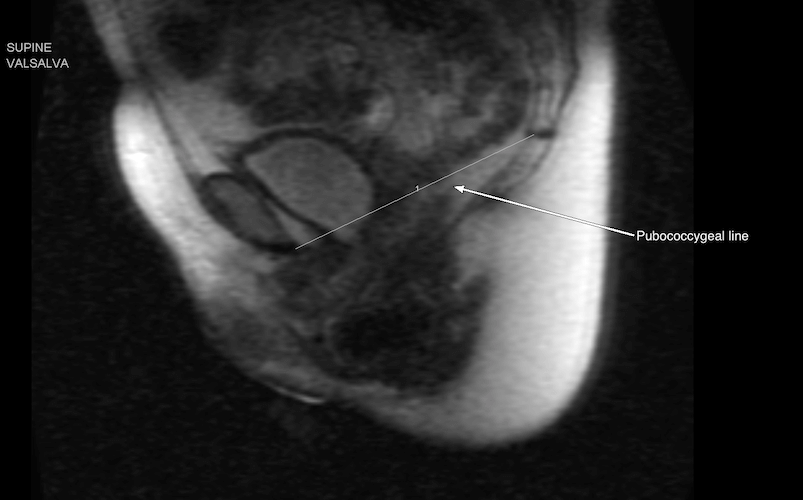

Sagittal MR image obtained of a supine patient performing the Valsalva maneuver. The descent of the urinary bladder, vagina, and rectum are compared to the pubococcygeal line.